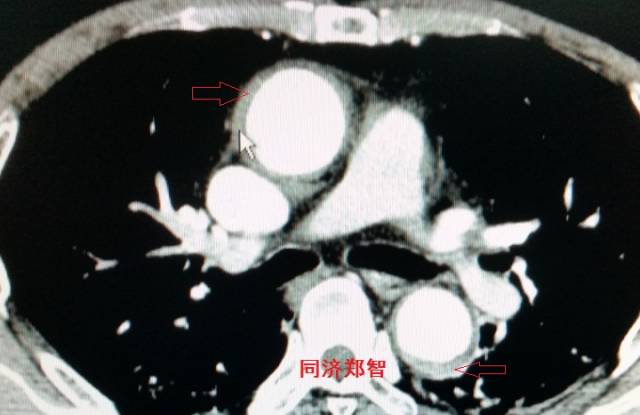

病例十

腹主动脉平扫CT提示正常外周一圈的钙化影中有内移的钙化影(红色箭头所示),CTA 证实为腹主动脉夹层。